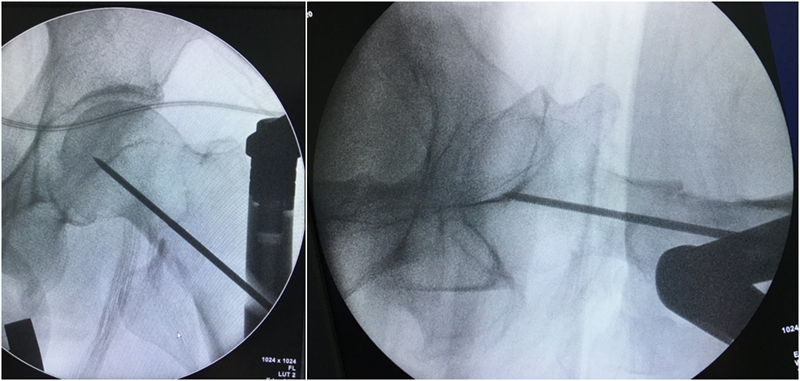

3、插入导针,扩隧钻扩隧:

(1)将保护套筒和钻头套筒置于进钉点,打入导针;扩髓,在扩髓钻插入开口处后,在其外侧放置一个保护器械,防止扩髓钻向外侧偏斜破坏股骨大转子的外侧皮质;扩髓时注意扩髓钻较主钉粗2mm。

(2)髓内钉的进钉点正好位于骨折线,常规开口插入髓内钉会使骨折线张开,导致髋内翻畸形,甚至内固定失效。

处理方法之一:先点压住外侧壁,让钻头缓慢进入,为髓内钉创造通道。同时还可以使进钉点尽量靠近完整的内侧骨质,避免髋内翻畸形的出现。

采用过度牵引方法是关键,先不要追求解剖复位。确定导针的位置以后,图A:将扩髓钻顶住近侧骨折块的外缘,开始扩髓;图B:扩髓钻打磨掉近侧骨折块外侧。

图8 A:将扩髓钻顶住近侧骨折块的外缘,开始扩髓;B:扩髓钻打磨掉近侧骨折块外侧。

然后放松牵引,解除过牵,骨折解剖复位以后再向远端扩髓、置钉,即可获得完美的复位固定。

处理方法之三:加大牵引,维持在过牵状态下进行扩髓。此时,骨折端受纵向牵引力的影像,侧向张开移位的幅度会明显减小。同时注意扩髓钻紧靠位于内测的近折端骨折块打开缺口。